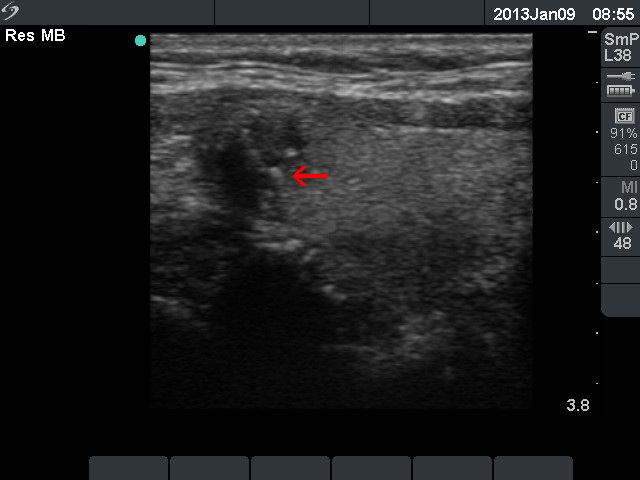

Follicular adenoma (histological diagnosis) - case 1056 |

Papillary carcinoma (histological diagnosis) - case 1074 |

The presentation of the granules is similar in these cases. However the benign lesion has several granules with dorsal tail, therefore these correspond more likely to comet-tail artifacts than to punctate echogenic foci. On the other hand, the complex structures in the malignant nodules are composed of multiple granules. It is worth comparing the figures marked with arrows.